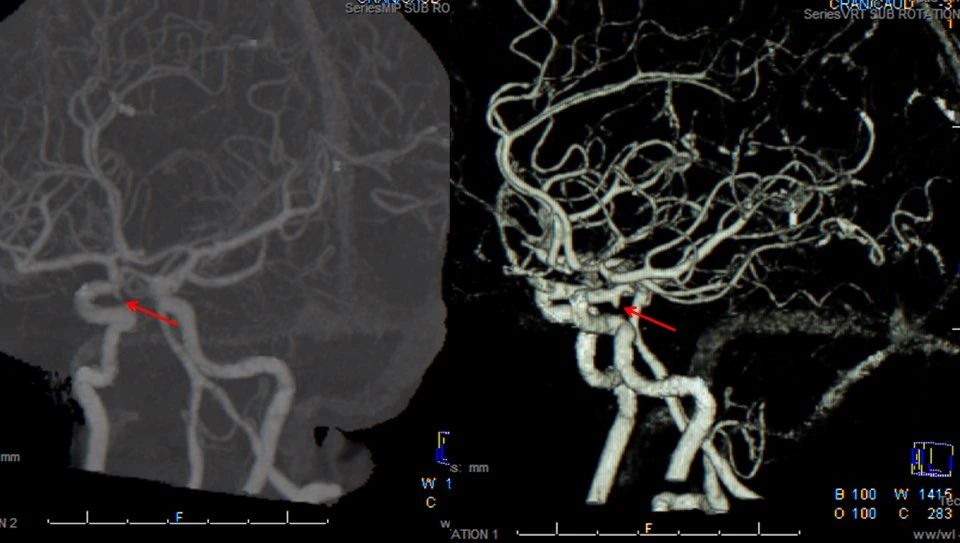

제이 : 방사선사는 일반적으로는 X-Ray 촬영을 하는 사람으로 알려져 있는데 ‘영상의학’을 전반적으로 아우르는 테크니션이라고 할 수 있어. X-Ray를 시작해서 경력이 쌓이면서 수술실에서 C-Arm 엑스레이, CT 스캔 MRI, 초음파 등의 검사를 진행하고 병변이 보이는 응급한 경우 의사에게 바로 리포트를 해서 조치를 취하게 해. 호주에서 2009년 영상의학 학사학위 유학을 시작하며 이 일에 연을 맺었어. 실무 경력은 한국에서 방사선 촬영병으로 2년, 호주의 요양병원에서 CARE NERSE로 4년, 그리고 졸업 후 방사선사로 1년 차로 총 7년 째 의료계에 종사하고 있어.

제이 : 그냥 무조건적으로 호주가 착한 나라라서 더 존중해주는 것은 아니야. 내가 봤을 때는 물리치료사나 방사선, 안경광학 등의 교육과정이 한국에 비해서 더 심화되어 있어서 그래. 영상의학을 예를 들면 한국의 방사선과 과정에 비교해서 훨씬 심화된 교육을 받아. 해부학도 엄청 빡세게 공부하고 영상을 찍는 것을 넘어서 다 판독할 줄 알아야 하거든. 혈관 하나하나, 근육 하나하나, 모든 인대들의 이름도 다 알아야 해. 의사 한 명이 독단적인 진단을 내리기 전 방사선사가 한번 더 판독을 함으로써 오류를 줄이고 환자의 생존율을 높이기 위함인 거야. 그런데 한국에서는 내가 방사선사라고 하니까 그냥 엑스레이 사진 찍는 아저씨구나, 하더라고. 방사선 공부한다고 하니까 왜 그런 거 하냐고 하는 사람도 있어서 이 일 한다고 말하기 싫을 때도 있었어. 방사능이랑 헷갈리다 보니 위험하고 험한 직업이라고 생각하기도 하고.

한국 군대에서 이런 일이 있었어. 정신과 전문의가 야간 당직일 때 어떤 환자의 가슴 사진을 찍어서 줬는데 그걸 도통 모르겠다는 얼굴로 보다가 그냥 보내려고 하는 거야. 내 눈에는 폐렴이 보이는데! 그래서 혹시 여기 이거 pneumonia sign 아닙니까? 하니까 어? 어.. 어! 그러네?! 입원시키자 그랬던 적도 있었어. 의사라고 해도 모든 분야의 전문가는 아니기 때문에 나 같은 각 분야 전문인력의 도움이 역할이 굉장히 중요해. 나라는 개인의 처우와 명예를 떠나서 환자들을 위해서. 한국은 아무래도 그런 면에서 아직은 인식이 좀 꽉 막힌 편이야.